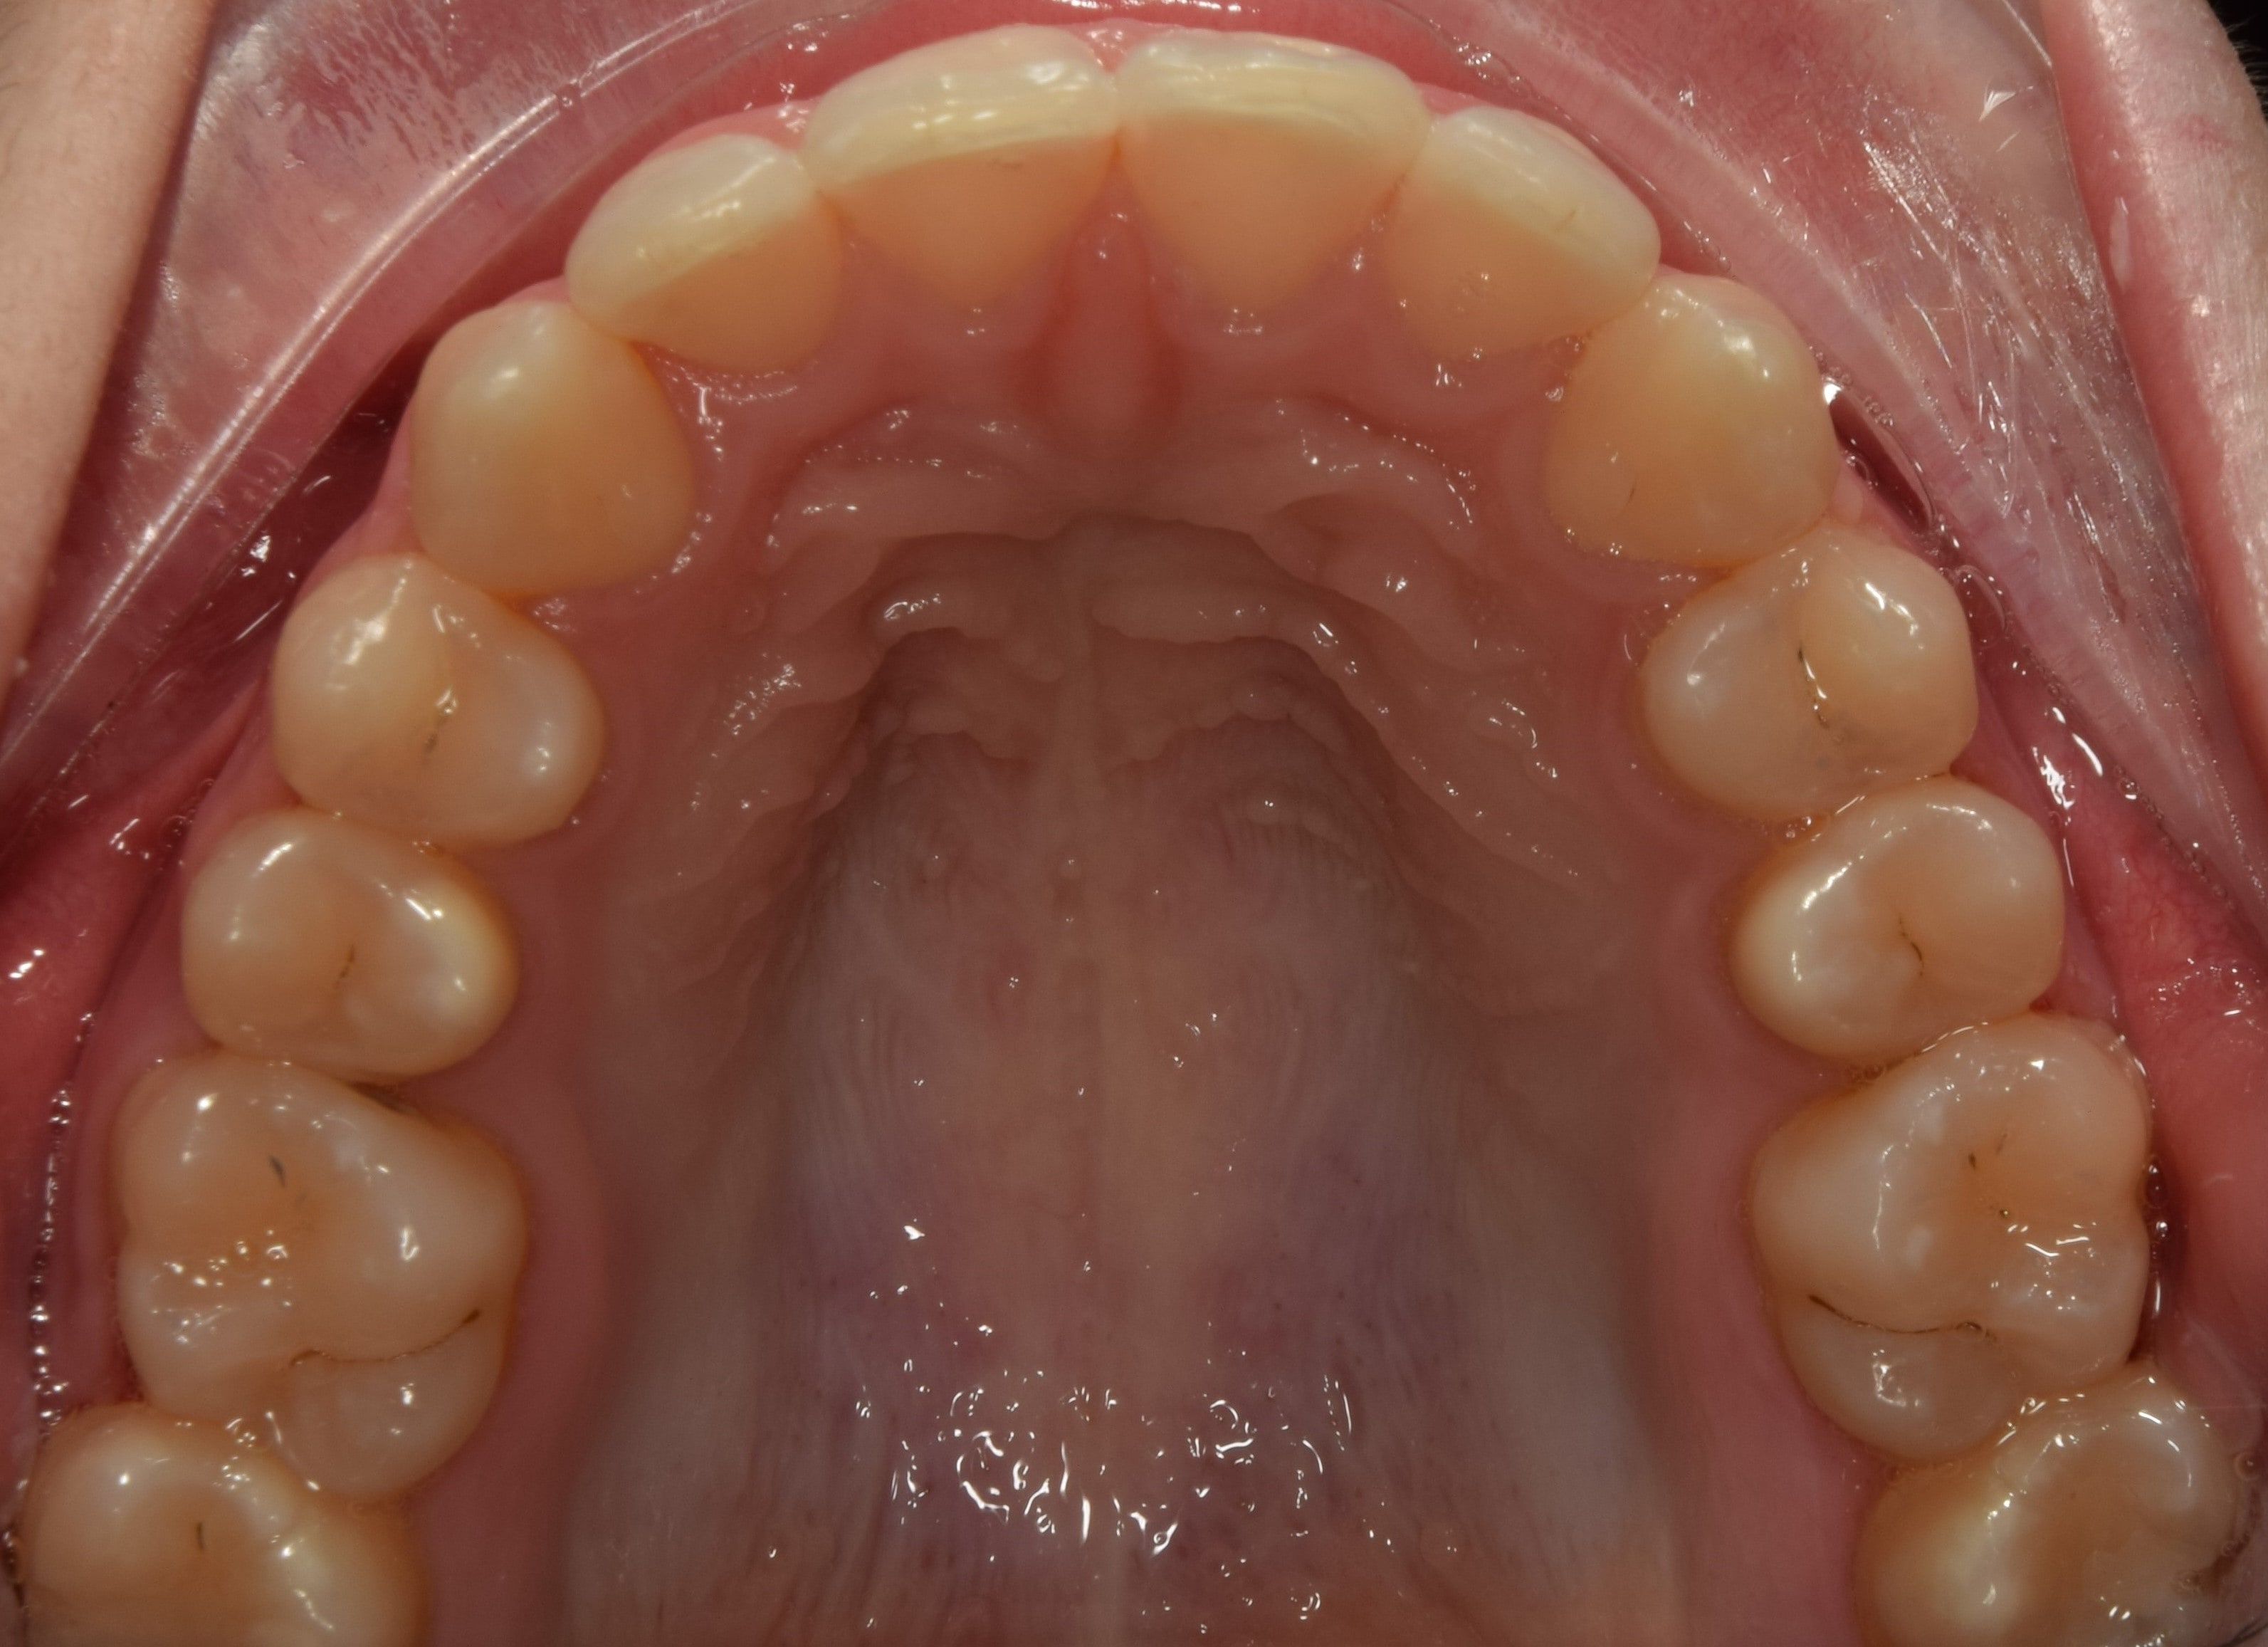

Sutura palatina mediana

A felső állcsont közepén elhelyezkedő csontvarrat. Fogszabályozási jelentősége, hogy a még nyitott állapotban lévő csontvarrat mentén történik a felső állcsont tágítása (hyrax). Ez a varrat kb. 12-13 éves korra elcsontosodik, és ezután kizárólag bonyolultabb készülékek segítségével nyitható újra, vagy szájsebészeti úton. A sutura palatina mediana mentén történt felső állcsont tágítás ténylegesen a felső állcsont alapját szélesíti, tehát nem csak a fogakat mozgatjuk a tágítás során. Ez a legkívánatosabb módja a tágításnak.